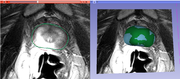

| 12:30, 21 June 2013 | ProstateResylt-MIT2013.png (file) | 351 KB | Result of prostate processing. Summer project week 2013 | 1 | |